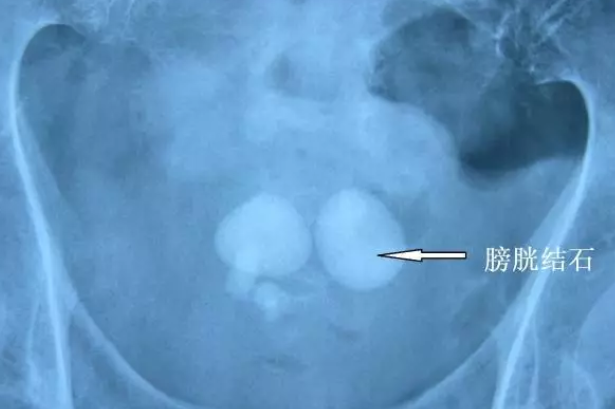

图片

多发性膀胱结石和单发膀胱结石